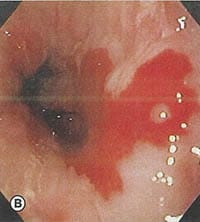

Υποψία για οισοφάγο Barrett τίθεται κατά την ενδοσκόπηση και πιστοποιείται με βιοψία και ιστολογική εξέταση. Φυσιολογικά το επιθήλιο του στομάχου είναι κυλινδρικό και η γαστροοισοφαγική συμβολή (Z-line), ευρίσκεται, κανονικά στο κατώτερο άκρο του οισοφάγου, ακριβώς πάνω από τις εγγύτερες πτυχώσεις μιας μικρής διαφραγματοκήλης, εάν αυτή είναι υπαρκτή.

Όμως στον οισοφάγο Barrett, ο άπω οισοφάγος επενδύεται με κυλινδρικό επιθήλιο, που επεκτείνεται προς τα πάνω για μία μεταβλητή απόσταση, συχνά από 3cm μέχρι 10cm αλλά και περιστασιακά εμπλέκει το μεγαλύτερο τμήμα του οισοφάγου. Το εγγύς όριο του οισοφάγου μπορεί να είναι οριζόντιο ή μπορεί να υπάρξουν ανώμαλες, συχνά σχήματος γλώσσας επεκτάσεις του κυλινδρικού επιθηλίου. Πολλοί ασθενείς έχουν νησίδια αναγεννητικού ή υπολειμματικού πλακώδους επιθηλίου, ενώ άλλοι παρουσιάζουν διάσπαρτα καλοήθη έλκη στην κυλινδρική περιοχή. Οισοφαγικές στενώσεις και οισοφαγίτιδα ίσως, να διαφαίνονται επί της ΝΕΑΣ συμβολής (πλακώδους – κυλινδρικού επιθηλίου). Επίσης, κατά την ενδοσκόπηση θα πρέπει να αναζητείται ένδειξη για αδενοκαρκίνωμα, όπως αυτή των οζιδίων ή μαζών.